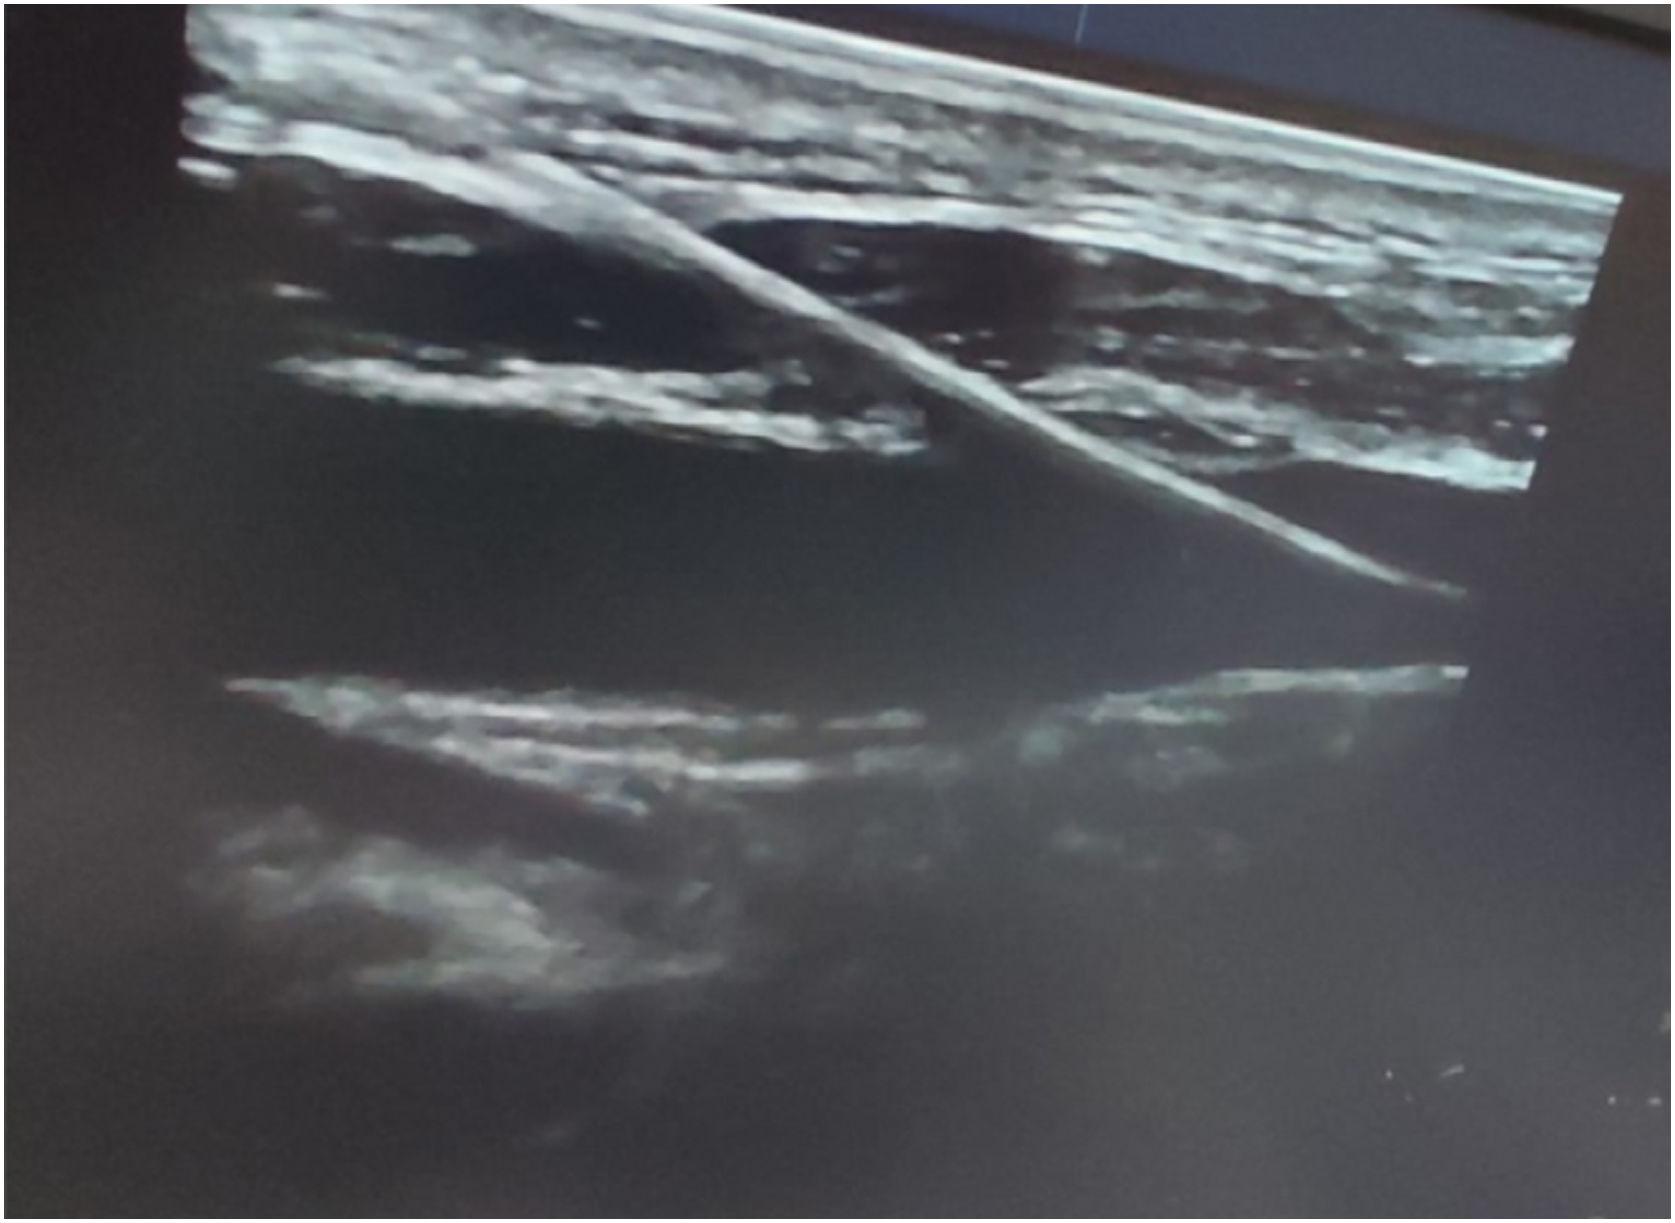

ResultsPatient ages ranged from 17 to 80 years with 56% being males. Urgent indications were found in around 22% without significant differences between groups. Regarding the time of performance, the ultrasound-guided method had slightly but significantly less time of performance (25.7 ± 4.3; range: 18−33) compared to the blind technique (26.9 ± 7.4; range: 15−45) (P-value < 0.001) with a higher but non-significant number of patients without complications (64% vs 52%; P-value = 0.2). Failure to insert the CVC into the IJV occurred in 12 patients (12%) with the blind technique and in eight patients (8%) with the ultrasound-guided technique (P-value = 0.04). Carotid artery puncture with neck hematoma occurred in only 8 (8%) patients with the blind technique (P-value = 0.04). Excess cost was consumed in only 36 patients (36%) in the blind technique group (P-value = 0.001).

ConclusionPoint-of-care ultrasonography bundle for CVC insertion is considered superior to, safer, and more cost-effective than the blind technique.